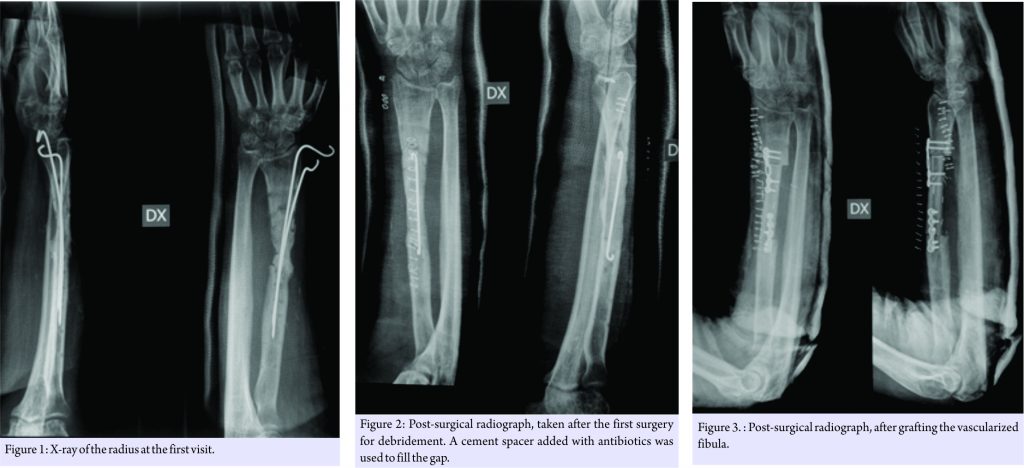

He presented at the Codivilla Hospital complaining of pain and presenting a non-suppurating fistula at the scar site of the previous operations. A radiograph was taken and showed a non-union and bone loss (Fig. 1). In November 2007, the patient underwent surgery aimed at completely debriding the site. A cement spacer containing gentamicin and clindamycin (Copal G+C, Heraeus, Hanau, Germany), along with vancomycin, was placed into the gap (Fig. 2). At this point, the surgical site was positive for Staphylococcus aureus. 3 months later, in February 2008, as a fistula developed again, the spacer was replaced with a new one (same source as the previous surgery). The antibiotic therapy was interrupted 2 weeks before spacer replacement for allowing bacteria strain identification. Before spacer replacement, a white blood cell scintigraphy, laboratory tests for inflammation, including erythrocyte sedimentation rate, C-reactive protein, and complete blood count were performed and radiography was taken. Based on the results of antibiograms, imipenem and vancomycin also were added, and oral antibiotics were also prescribed (ciprofloxacin, 750 mg twice a day). 3 months later, in May 2008, the fistula had disappeared, and the patient’s leukocyte scintigraphy was negative. After 3 more months, in August 2008, the patient underwent reconstruction using a vascularized fibula graft (Fig. 3). At the subsequent control appointments, radiographs showed non-union of the graft (Fig. 4). 8 months later, in April 2009, the graft and the osteosynthesis devices that had been concomitantly placed were removed, and a third spacer was positioned.